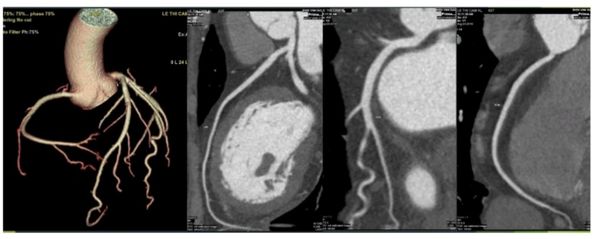

Cắt lớp vi tính động mạch vành là một kỹ thuật thu hình tim – động mạch vành 3 chiều (3D) bằng cách sử dụng máy cắt lớp vi tính thế hệ mới, cho ra hình ảnh rõ nét và chính xác, giúp chẩn đoán bệnh lý tim – động mạch vành.

Độ chính xác >90% ở hầu hết các nghiên cứu lớn trên thế giới và sử dụng hệ thống tiên tiến tương tự tại bệnh viện chúng tôi.